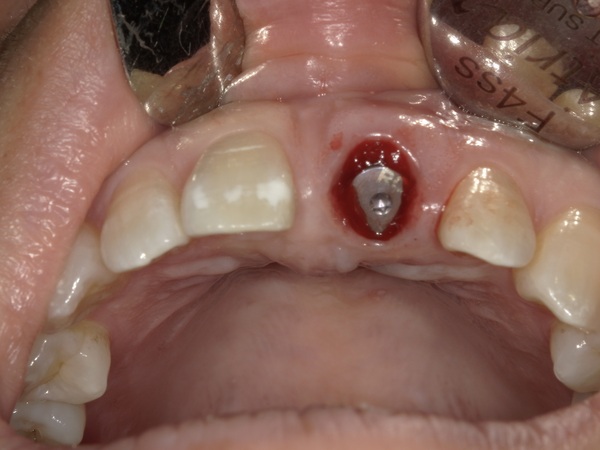

こちらがインプラントを入れた後の写真になります。

切開を全くせずにインプラントを入れているので、ほとんど出血がないのが分かるかと思います。また術後にほとんど痛みも腫れも出なかったようです。